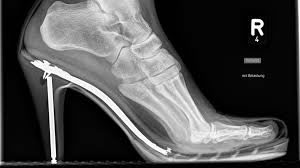

O joanete é a patologia mais comum que ocorre nos pés dos adultos hoje em dia (30 % da população moderna possui algum grau de deformidade), principalmente nas mulheres que utilizam calçados de salto alto e bico fino, exercendo assim um fator extrínseco (externo) importante, que propicia a degeneração da articulação do primeiro dedo e auxilia para que aconteça tal deformidade. É 10 vezes mais comum nas mulheres do que nos homens!

Existem também outros fatores que contribuem para que a deformidade ocorra, como: doenças degenerativas (artrite reumatoide, gota, etc..), hereditariedade (pé plano, herança familiar, frouxidão ligamentar familiar) e alterações neurológicas (derrame, paralisia cerebral, trauma de coluna (medular).

Além da deformidade, o paciente com joanete pode apresentar uma calosidade na borda interna do pé (ao lado da articulação desviada) podendo ser dolorosa e incômoda para o uso de alguns tipos de calçados. Também pode apresentar deformidades nos outros dedos do pé e calosidades plantares.